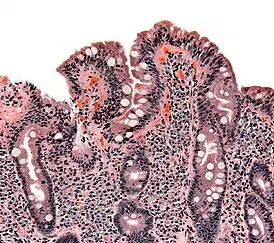

![]() Биопсия тонкого кишечника у больного с целиакией. Видна уплощенная форма ворсинок, лейкоцитарная инфильтрация и гиперплазия крипт. | |